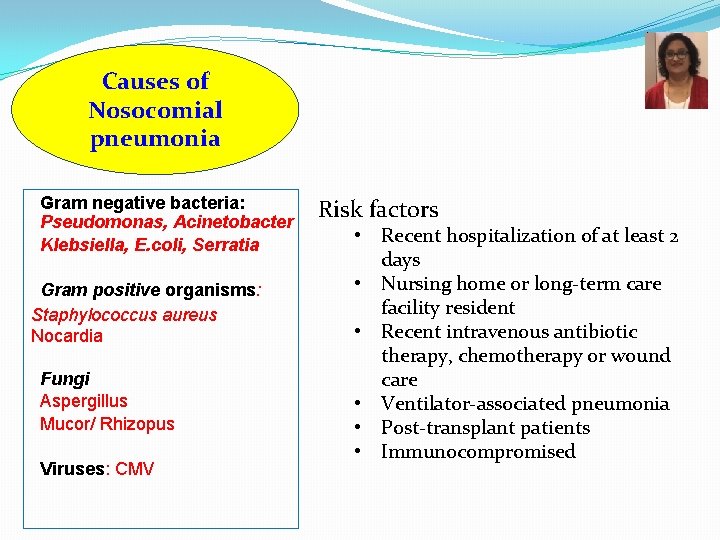

Causes of Nosocomial pneumonia Gram negative bacteria: Pseudomonas, Acinetobacter Klebsiella, E. coli, Serratia Gram positive organisms: Staphylococcus aureus Nocardia Fungi Aspergillus Mucor/ Rhizopus Viruses: CMV Risk factors • Recent hospitalization of at least 2 days • Nursing home or long-term care facility resident • Recent intravenous antibiotic therapy, chemotherapy or wound care • Ventilator-associated pneumonia • Post-transplant patients • Immunocompromised